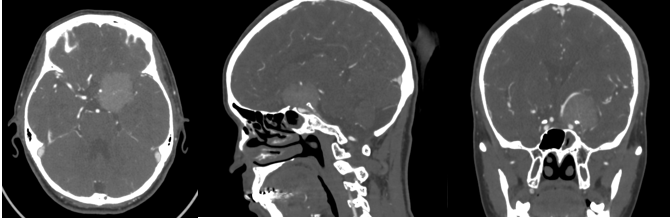

现病史:患者20天前无明显原因出现鼻酸,伴有异味感,继之出现全身不适,呈发作性,每次持续约1分钟左右,发作时意识清、精神可,对发病时情况记忆模糊,共发作3-4次,无意识模糊、复视。颅脑MRI平扫+强化示:鞍上池左侧可见不规则等T1等T2信号影,DWI呈等信号;明显均匀强化,与前床突、颈内动脉关系密切。

诊断:左侧蝶骨嵴脑膜瘤;继发性癫痫。

Al-Mefty教授根据肿瘤的起源和肿瘤与颈内动脉之间是否存在蛛网膜界面,将前床突-蝶骨嵴内侧的脑膜瘤分为三型,这是目前最为经典和广泛认可的分型。ICA在前床突内、下侧方从海绵窦穿出,经过内环与外环(或上环与下环)而后进入硬膜下腔,内外环之间约1-2mm,该节段缺少蛛网膜覆盖。起源于这一小段的脑膜瘤被分为1型前床突脑膜瘤。1型典型的生长方式是包裹ICA,并向颈内动脉分叉部方向生长,包裹近端大脑中动脉。由于肿瘤与颈内动脉之间缺乏蛛网膜,所以它紧密黏附在ICA的外膜上,以至于分离困难,导致手术治愈率相对较低。该患者主体属于1型前床突脑膜瘤,但是因其部分侵入视神经管内,兼有3型的特点,严格讲其属于1-3复合型脑膜瘤。该患者经左侧翼点入路肿瘤切除术,实现肿瘤近全切除,术后未再出现癫痫发作,脑电图无异常,后逐渐减用停用抗癫痫药物,现已持续随访4年余,未见肿瘤复发。